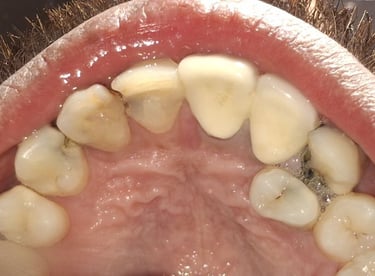

Tooth Colored Filling in Shyamal, Ahmedabad

Tooth-colored fillings are used to restore decayed or broken teeth while maintaining a natural appearance. These fillings blend seamlessly with your tooth color and help preserve your smile.

Before

After

All images shown here are real tooth colored filling cases treated at our clinic with patient consent.

At Shree Dental Care, cosmetic fillings are placed carefully with a focus on comfort, precision and long-term durability. We ensure minimal tooth cutting and natural-looking results.

If you are looking for aesthetic tooth colored filling in Shyamal, Ahmedabad, you can book an appointment with our clinic.